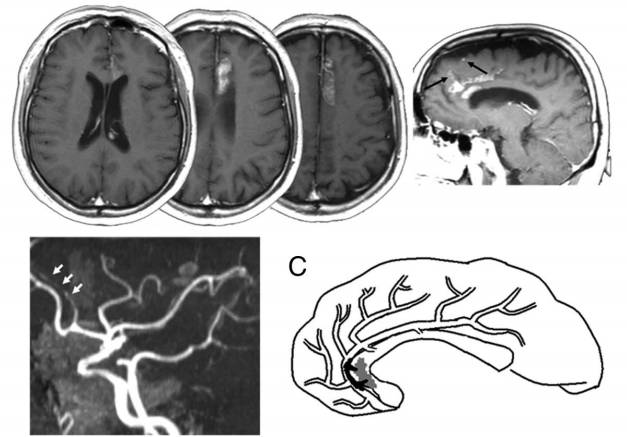

图4 增强磁共振扫描提示胼胝体和扣带回的梗死,矢状位图像提示额上回也有受累。MRA提示大脑前动脉A2和A3段闭塞。C为模式图,黑色部分为血栓,灰色部分为梗死区。